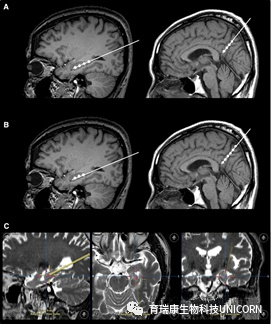

不仅如此,干细胞输注治疗安全可行。一项“立体定向脑内注射人间充质干细胞治疗AD病人”的临床试验结果表明,在治疗结束后的24个月随访时间内,患者没有出现与干细胞治疗相关的严重的不良反应。

图片

△ 立体定向注射

淀粉样蛋白负荷、葡萄糖代谢及CFS生物标志物水平